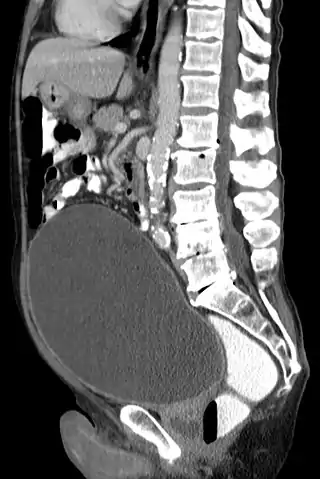

La retención urinaria es la incapacidad de un individuo de orinar pese a tener la vejiga llena, con su consecuente aumento de volumen, lo que se conoce como globo vesical. Antiguamente se denominaba iscuria.[1]

El examen físico muestra una masa en el bajo vientre, por encima del pubis, redondeada, extendida y con un sonido mate a la percusión.

La más frecuente de las complicaciones es la infección urinaria: cistitis primeramente y posteriormente pielonefritis. Cuando es crónica, la retención provoca una distensión de la vejiga con atonía del detrusor, hipertrofia del detrusor o formación divertículos vesicales. La retención urinaria podría provocar un reflujo de la orina hacia los riñones, que causaría una hidronefrosis.